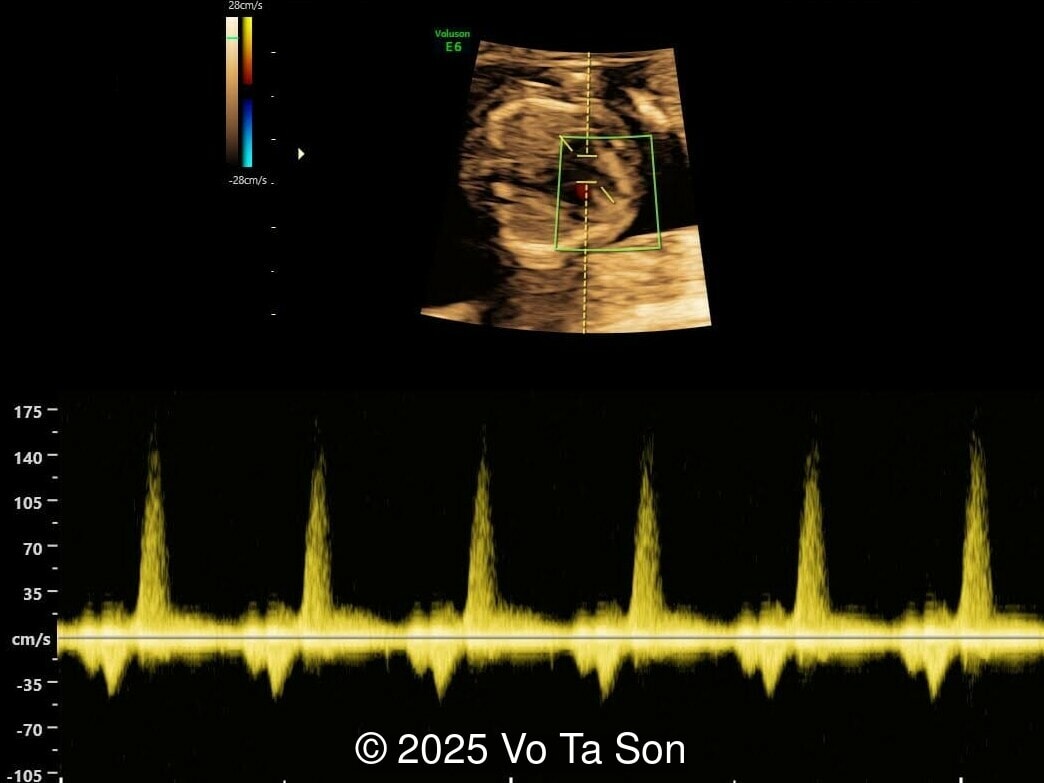

We present a case of Triploidy with a 69,XXY chromosomal complement and open spina bifida in the first trimester.

• Ventricular septal defect (VSD)

• Tricuspid valve regurgitation

• Right aortic arch

If a triploid fetus survives to the second trimester, structural anomalies can be detected by ultrasound and occur in approximately 44-49% of fetuses [4,11]. These include anomalies of the extremities (syndactyly of the third and fourth fingers, clubfeet), central nervous system (holoprosencephaly, Dandy-Walker malformation, agenesis of the corpus callosum, neural tube defects), face (micrognathia, microphthalmia), as well as omphalocele, cardiac anomalies, and renal anomalies [6,7]. The most common findings are syndacyly, occurring in approximately 70% of cases [11], and central nervous system anomalies, which are found in approximately 40% of cases [11], with myelomeningocele found in 9-13% of fetuses with triploidy [8,11-12]. Cardiac defects occur in 13%, of which 9% are ventricular septal defect [11]. If these defects are seen in a growth-restricted fetus, triploidy should be considered in the differential diagnosis and amniocentesis offered, especially if the placenta is enlarged and contains cysts. Features of a partial hydatidiform mole occurs in 24-33% of cases with triploidy [4,11]. Additionally, theca lutein cysts may develop in the maternal ovaries due to high levels of human chorionic gonadotropin [6,7].